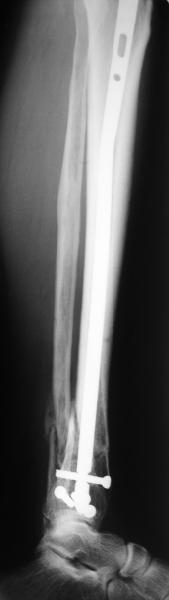

In delayed cases acute length restoration performed only in the tibia may leave the fibula shortened thus change the mortise. So it is reasonable to restore length of both bones simultaneously by distractor and fix the fibula not with open reduction and plating but just by a single perQ screw. Example attached.

At least both the ankle mortise and tibial alignment look acceptable, don't they?

I am just trying to illustrate that prevention of 1)tibial valgus and 2)loss of reduction can be provided without fibular plating. Small changes of conventional nailing techniques allow to maintain reduction of the tibia reliably without adjunctive fibular stabilization.